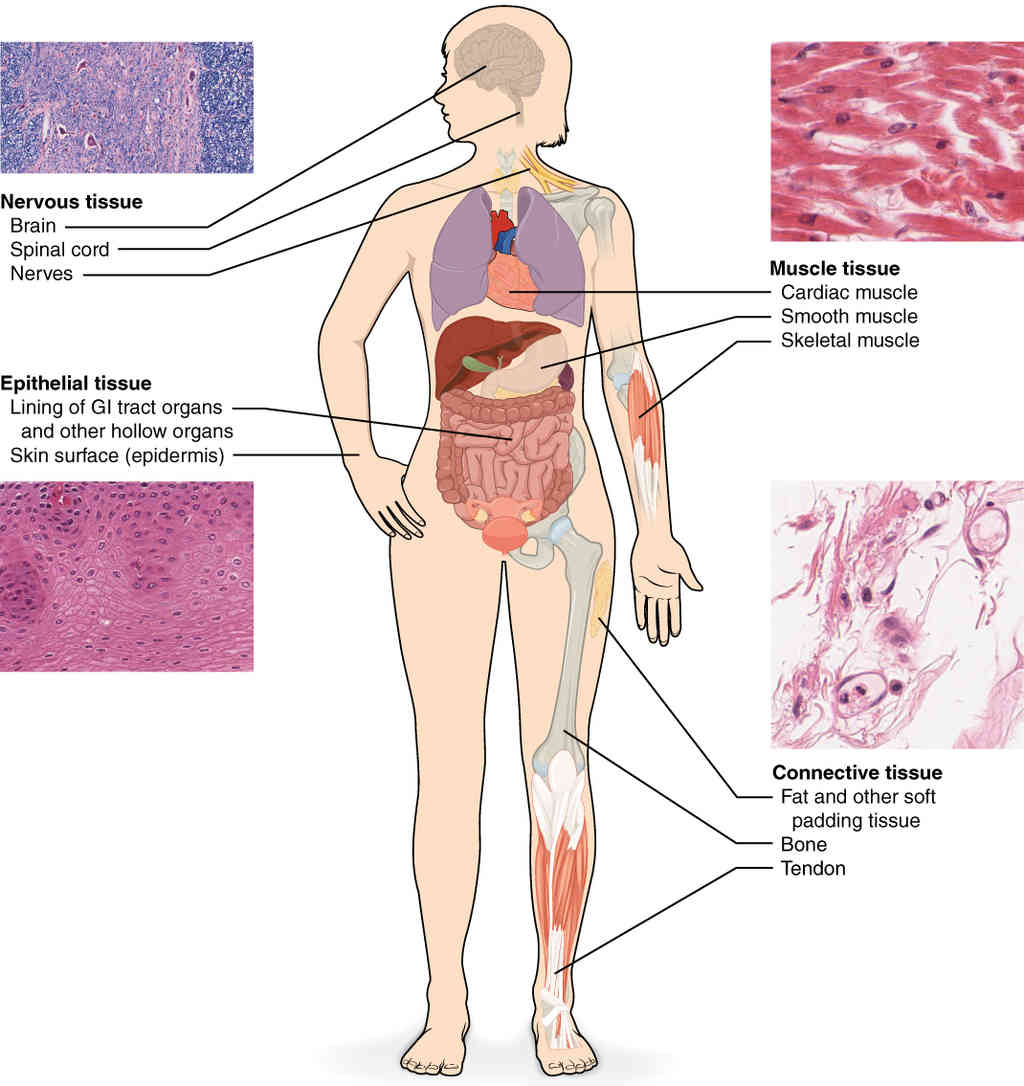

This page is under construction. For now, it is just a resource of the images found in the OpenStax Anatomy and Physiology Handbook. It wil slowly change into a revision tool. Each slide has a number. Use this to refer to the slide. When completed, it will have an unlabelled section, with labelled slides in parallel. On the unlabelled slides, write your answer and use the labelled slide to assess yourself. Keep track by also noting the number on each slide. Improvement at each attempt is important, more so than full marks on a first attempt.